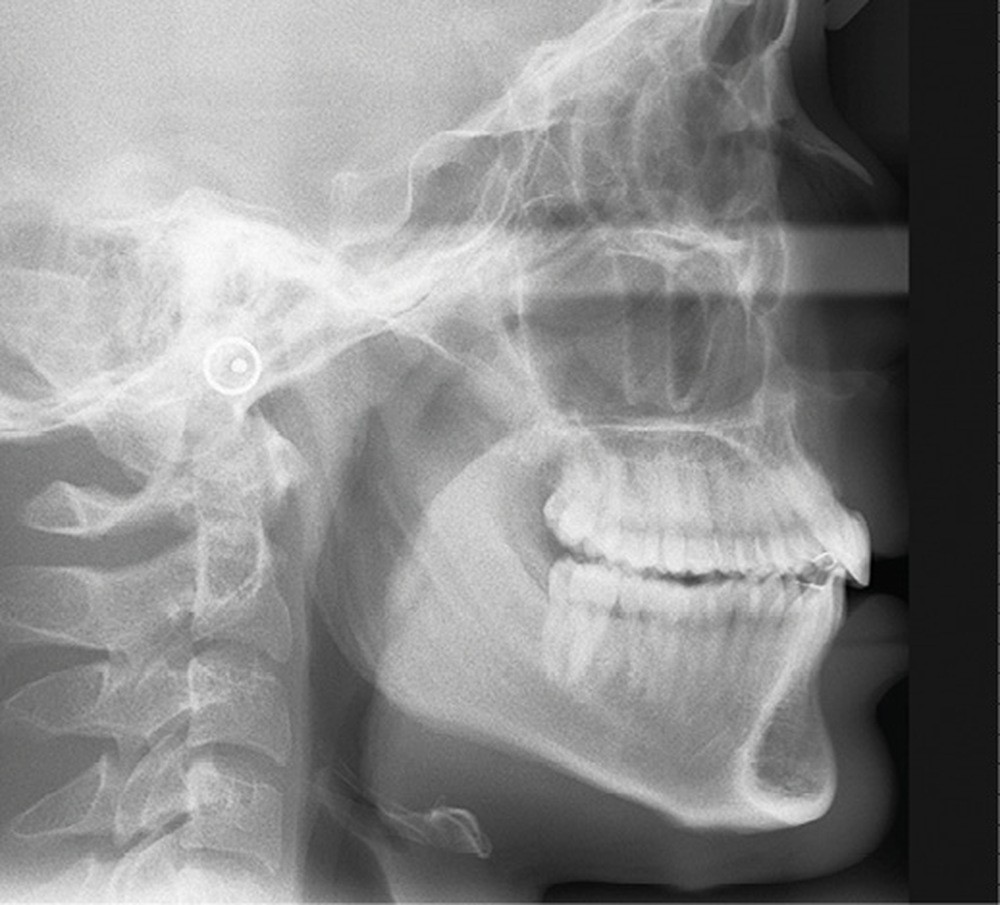

Le profil est convexe et associé à une inocclusion labiale au repos. Il s’agit d’une classe II squelettique sur un schéma facial normodivergent. Les rapports occlusaux sont de classe II bilatérale (complète au niveau molaire) avec des incisives inférieures vestibulo-versées. La 21 est géminée et la 11 vraisemblablement fusionnée avec un germe surnuméraire, sans altération de la formule dentaire. Du fait du diamètre mésiodistal fortement augmenté des incisives centrales, et du manque de place à l’arcade maxillaire qui en découle, les 12 et 22 sont en inversé d’occlusion en palato position. Les 53 et 63 sont persistantes sur l’arcade avec une inclusion en transposition incomplète de la 13, dont la cuspide se situe entre la racine de la 12 et celle de la 11 résorbée (fig. 1d-g).